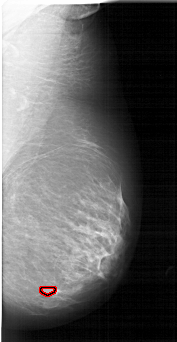

FILE: A_1739_1.RIGHT_CC.OVERLAY

TOTAL_ABNORMALITIES 1

ABNORMALITY 1

LESION_TYPE MASS SHAPE LOBULATED MARGINS CIRCUMSCRIBED

ASSESSMENT 3

SUBTLETY 1

PATHOLOGY BENIGN

TOTAL_OUTLINES 1

BOUNDARY